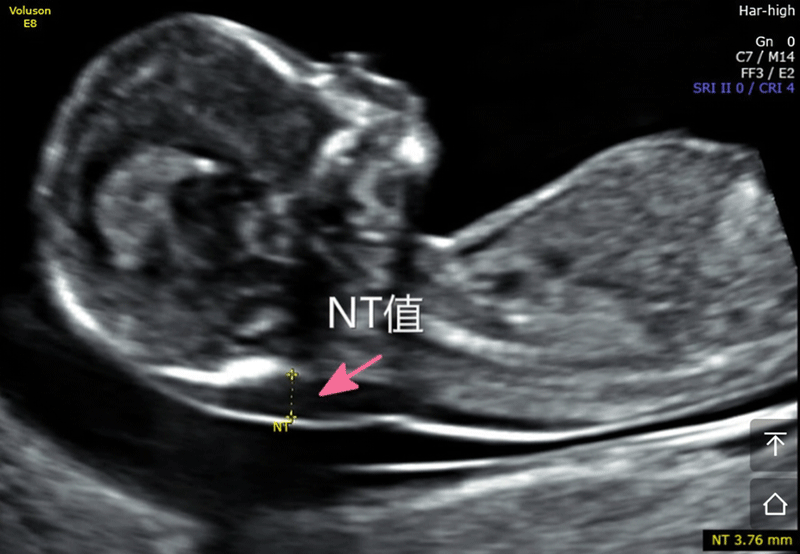

nt是胎儿颈后透明袋的简称,全称为(nuchal teanslucency),nt检查就是胎儿颈后透明带检查,检查胎儿颈后部皮下组织内液体积聚的厚度。

nt检查的主要作用就是获得nt值,通过nt值诊断胎儿是否正常,是否有染色体疾病和其他原因造成胎儿畸形,如果通过nt值提示胎儿有异常,在做四维彩超和唐氏筛查的时候将会重点关注。

nt检查正常值

nt检查正常值一般是在≤2.5mm,只要通过nt检查发现nt值在正常值范围内,就可不用担心了,nt检查属于一次检查。